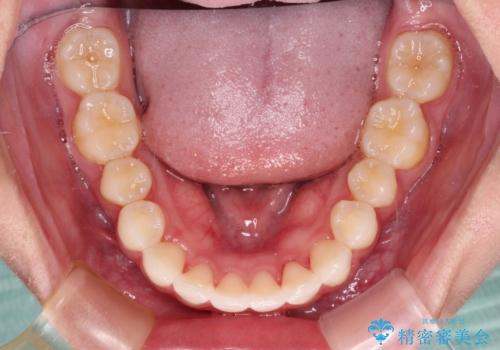

- 前歯2本が飛び出してることを気にして来院された患者様です。

全体的に黄ばんだ歯の色も気になるとのことで、マウスピース矯正により飛び出した前歯を治しつつ、ホームホワイトニングを併用して黄ばみを解消していくこととしました。

歯と歯の間を削ることで、飛び出した前歯が引っ込み、スッキリとした口元となりました。

歯の黄ばみも改善され、明るい歯並びとなりました。